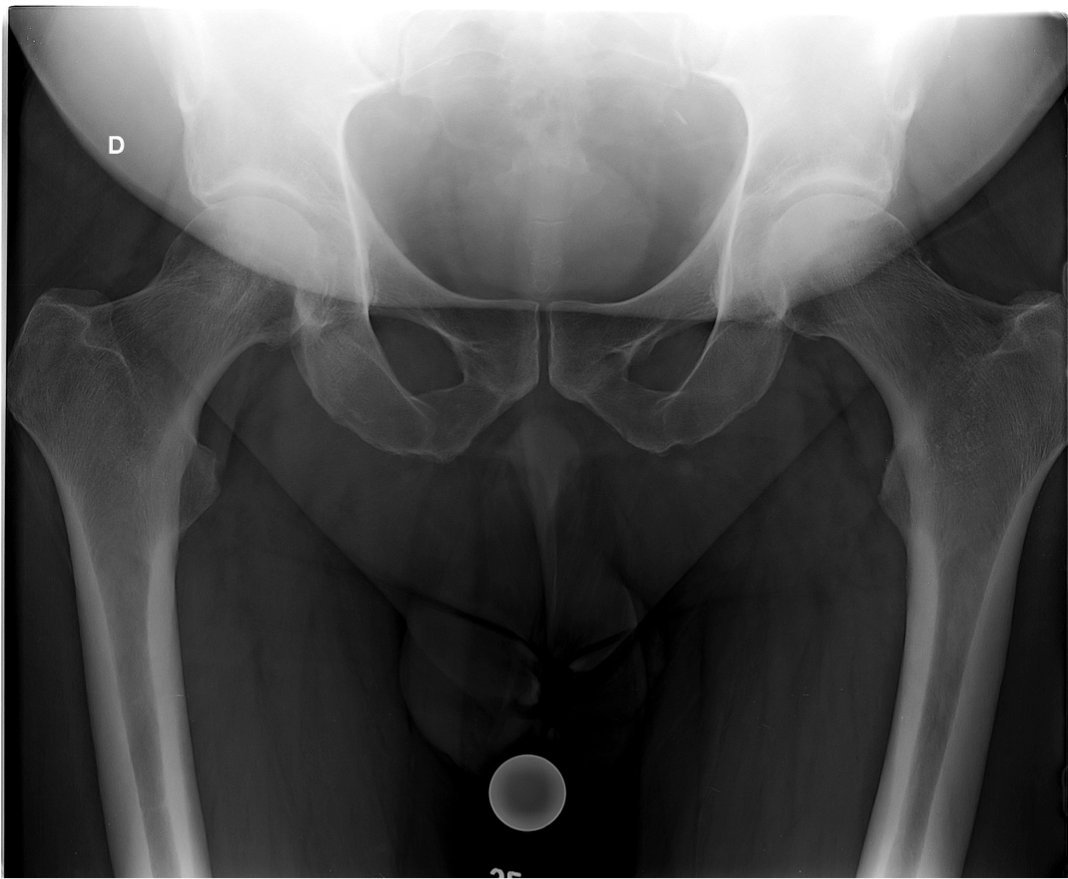

During hip arthroplasty (THR) implantation, restoration of the femoral lever arm (offset) is a crucial element in order to maintain the stability of the prosthetic joint, improve joint amplitudes and optimize the efficiency and power of the gluteal muscles [1,2]. This last point is essential, especially when the implantation is performed on a population of young subjects who wish to resume their sports activities. Indeed, adequate gluteal tension is essential for resuming activities such as running or sports with impulses on the lower limb. A value of 40 mm is commonly accepted as the upper limit of the mean femoral offset [2]. Hips with a high lever arm are very frequently accompanied by a long femoral neck and are most often found in young men and rarely in women. This is referred to as "long-neck coxa vara".

Prosthetic replacement of these hips with increased femoral offset and long necks is difficult, because it exposes the patient to many risks: instability, lameness, lengthening to tighten the gluteals and unevenness of length, and muscle failure if the offset is not restored [2]. Few non-modular femoral pivots can restore an offset of more than 40 mm. When this is possible with specific stems with a reduced neck-shaft angle, the survival rate of these implants does not seem to be as favourable as the standard offset version, because of the increase in the varus femoral moment. Other options exist: custom-made implants, short stems, trochanterotomy for distalization and re-tensioning of the gluteals, hip resurfacing (HRT), etc. The latter, which we use on a daily basis in the department, seems in this context to represent an attractive alternative, since it allows automatic reconstruction of the joint morphology. The HTR has many theoretical advantages over conventional total hip replacements: preservation of the femoral bone stock, integrity of the femoral shaft, no risk of significant elongation (variations being < 5 mm) and instability, ease of subsequent revision surgery, resumption of sports with impact, etc. [3]. Furthermore, it should be remembered that the frontal position of the femoral THR implant should be slightly valgus (7°) in relation to the native neck angle. Thus, a THR implanted on a hip in 114° vara will have a frontal position of about 120°. This valgus position transforms the shear forces into compression forces exerted on the femoral neck, which appears to be beneficial from a biomechanical point of view and for the durability of the femoral fixation.

We have therefore analysed the reproduction of the femoral morphology of an implanted THR in a population of young and athletic patients with a coxa vara hip with increased femoral offset, based on a prospective radiographic study.